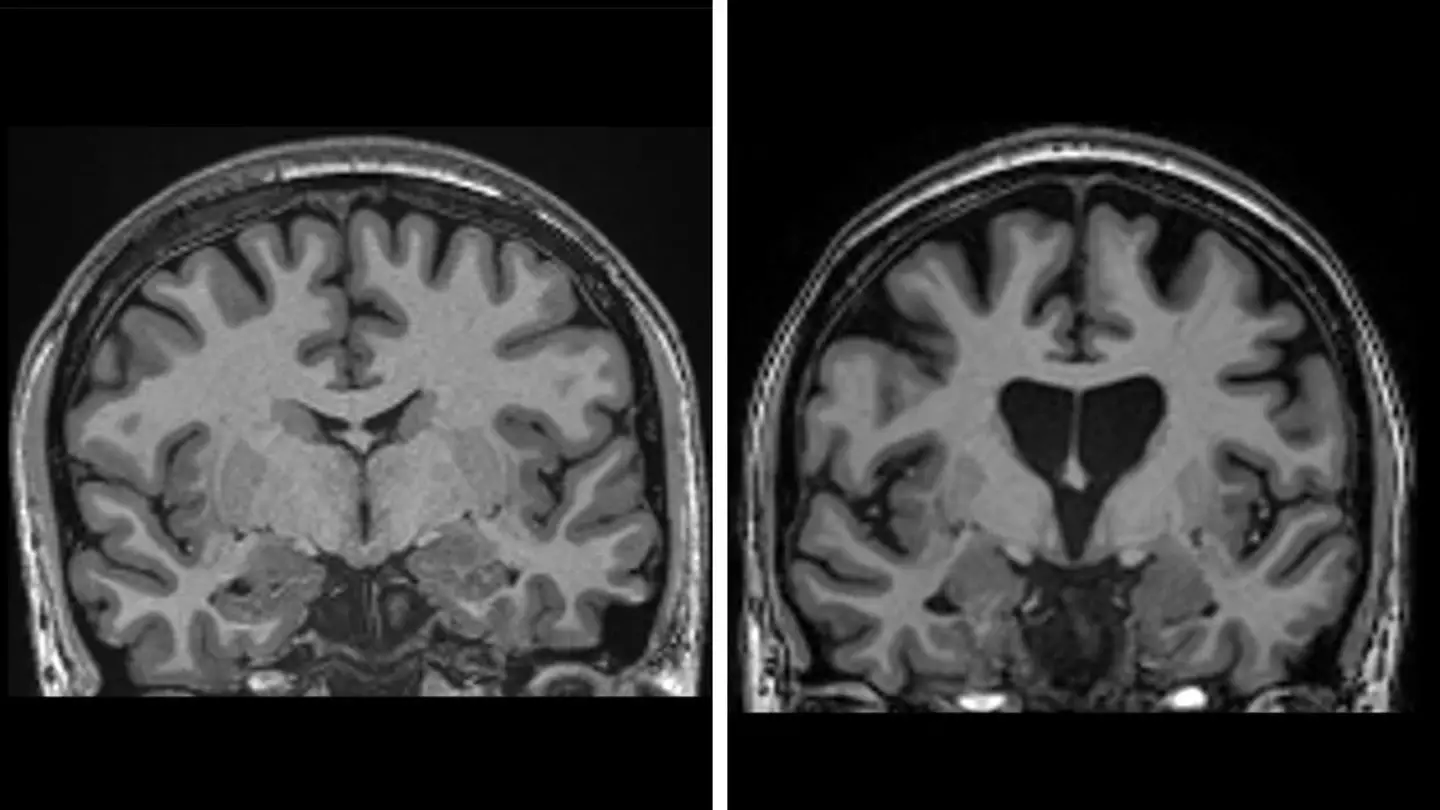

Doctors have achieved the first successful treatment of Huntington’s disease, a devastating genetic disorder that progressively destroys brain cells and mirrors symptoms of dementia, Parkinson’s, and motor neuron disease. The breakthrough involved a form of gene therapy delivered through 12 to 19 hours of intricate brain surgery. While the procedure is expected to be costly, it has proven safe. Data shows that three years post-surgery, the therapy slowed disease progression by an average of 75%.